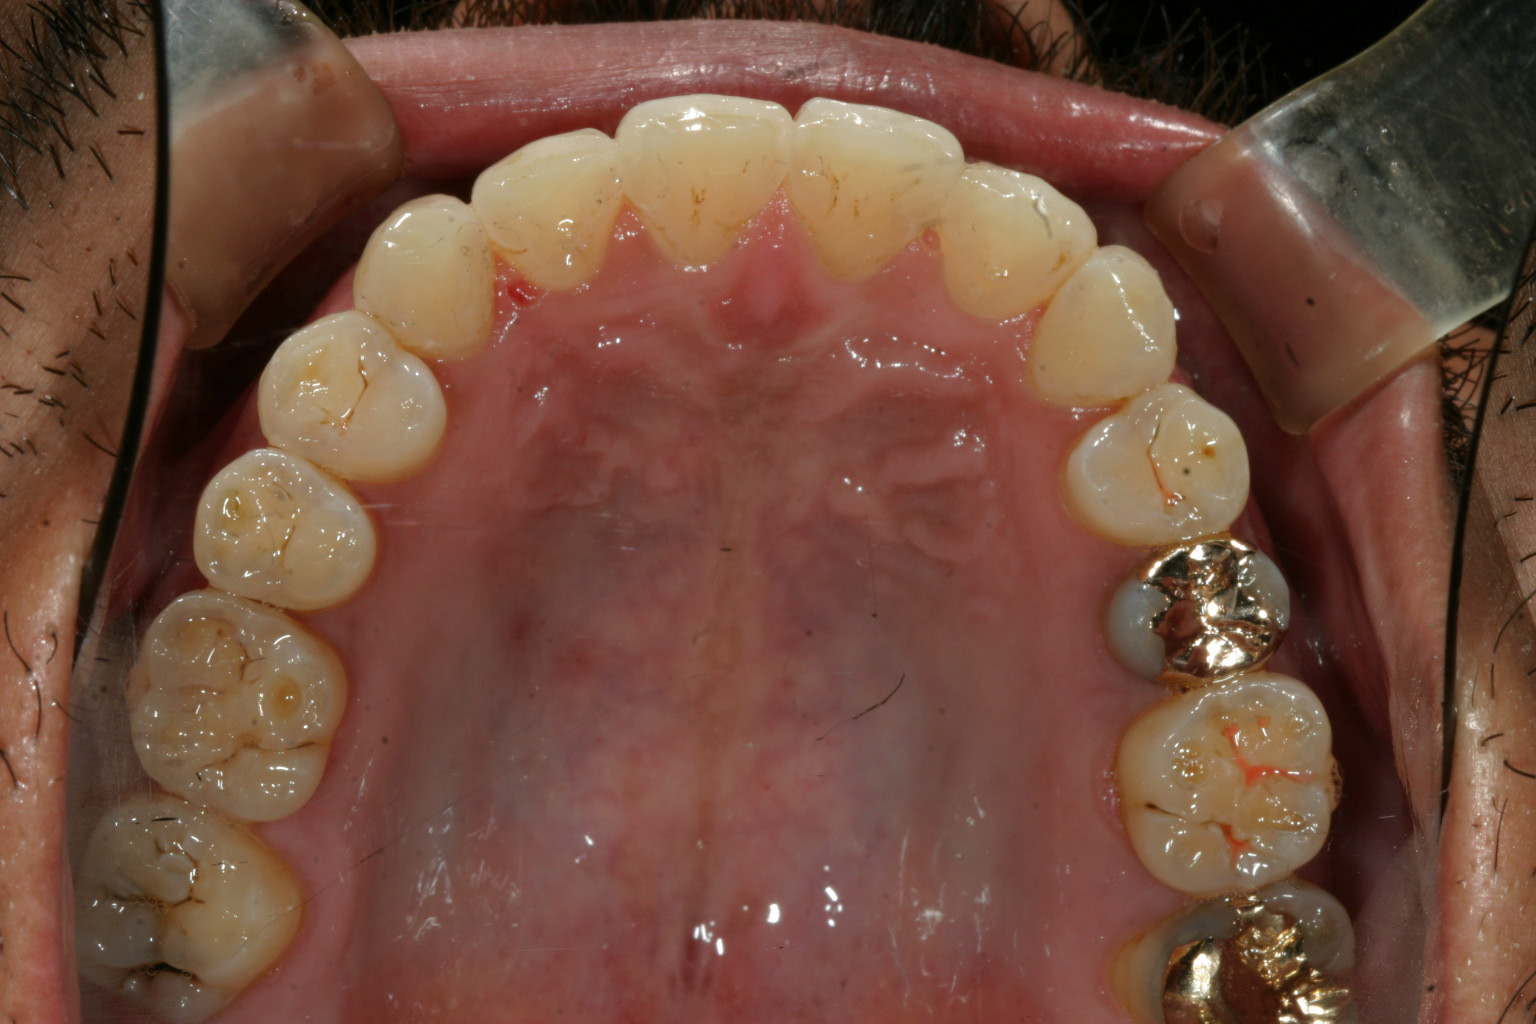

右の犬歯の突出が目立ちます。

インビザラインにて右側臼歯遠心移動(右側の大臼歯から順番に歯を後ろに下げて犬歯の入るスペースを確保する方法)